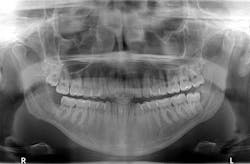

The same patient presents with this chief complaint: “Pain in lower right side of jaw that has progressively been getting worse over the course of the last two to three months; it feels like I have an infection in my wisdom tooth."

A panoramic is taken, and a large radiolucent lesion is noted to extend from the distal of no. 1 to the distal of no. 32. A significant amount of bone destruction in the mandible is observed. Furthermore, a radiolucency is present distal to the crown on no. 17. Clinically, there is inflamed tissue circa on partially erupted no. 32 that extends up to the distal of no. 2. The area is tender to palpation and unremarkable extraorally (figure 2).